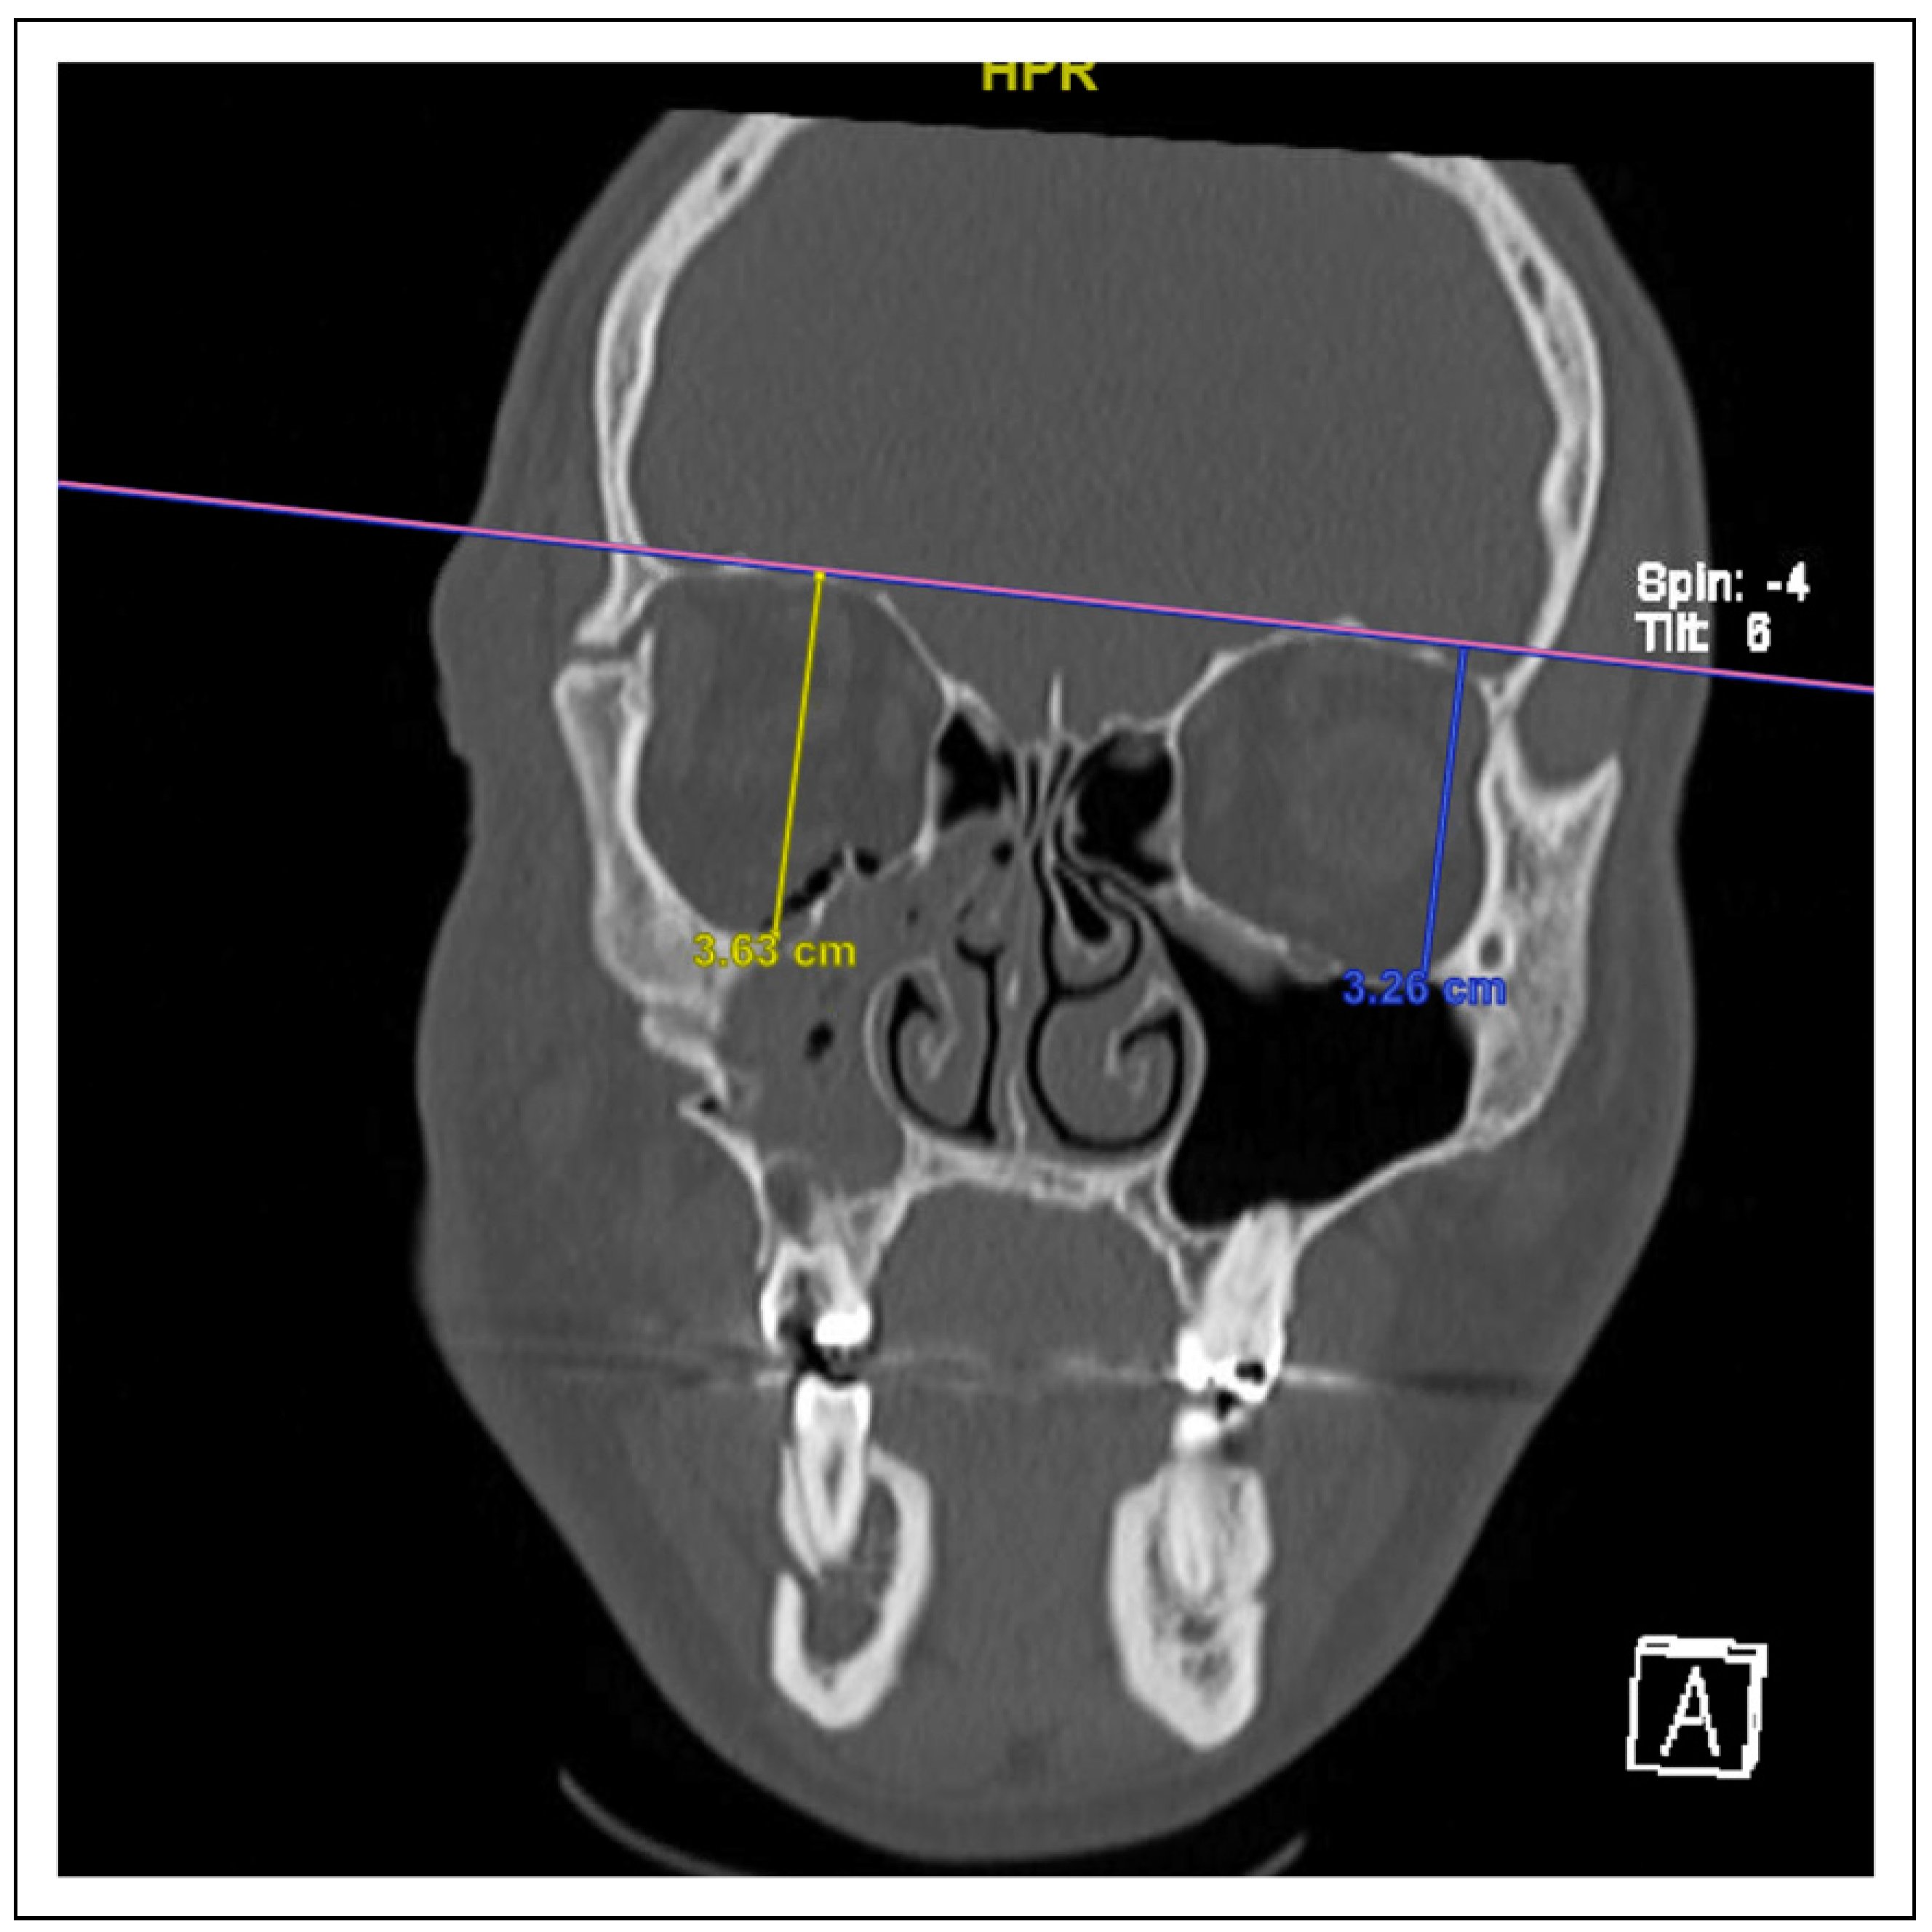

Figure 1. A photo of lateral maxillary wall impaction.

Computed tomography imaging characteristics of the fractures at initial presentation were similarly documented. Data elements measured in this study were (1) medial displacement or impaction of the lateral wall of the maxillary sinus (Figure 1), (2) zygoma angle of rotation (Figure 2), (3) anterior-posterior (AP) displacement of the zygoma (Figure 3), (3) cranial-caudal or vertical displacement of the zygoma (Figure 4), and (4) lateral-medial displacement (LM) of the zygoma (Figure 5). For all vector measurements, the uninjured side served as an internal control.

Lateral Maxillary Wall Impaction

Lateral maxillary wall impaction on radiographic imaging most significantly predicted malar changes (OR = 1.36,P < .001) and appreciable displacement or step-off of the infraorbital rim (OR = 1.23, P < .01). Specifically, for every 1-mm increase in maxillary wall impaction, patients experienced a 1.36-fold or 1.23-fold increase in the odds of symptomatic malar changes or step-off, respectively. Patients with malar flattening on examination experienced an average of 6.3 mm of lateral maxillary wall impaction, compared to 3.3 mm in those who did not present with obvious malar changes. Meanwhile, patients with infraorbital step-off experienced an average 5.8 mm of lateral maxillary wall impaction, and those without step-off experienced an average 3.6 mm of impaction. Other symptomatology, including malocclusion, trismus, diplopia, enophthalmos or orbital dystopia, and sensory symptoms, were not predicted by lateral maxillary wall impaction.

When analyzing the various possible displacement vectors for patients with ZMC fractures, we found the critical vectors that significantly predicted clinical symptomatology were lateral maxillary wall impaction (Figure 1), AP displacement (Figure 3), and vertical displacement (Figure 4). LM displacement (Figure 5) did not demonstrate a statistically significant association with any of our collected clinical variables.

Lateral maxillary wall impaction exhibited 1.36 times increased odds for malar changes (OR = 1.36, P < .001) and 1.23 times increased odds for visible or palpable bony step-off (OR = 1.23, P < .01) for every millimeter of displacement. The lateral maxillary wall is the key component of the zygomaticomaxillary buttress which functions to hold the zygoma in position. The authors hypothesize that ZMC fractures associated with a significant medial displacement of the lateral maxillary wall can serve as a surrogate marker for ZMC instability, and, in particular, disruption of the ZM buttress, which leads to greater displacement of the zygoma body and thereby malar changes. The importance of the ZM buttress for clinically significant displacement in ZMC fractures has been cited before. Prabhu et al. reported displacement along the ZM buttress to be most closely related to rotational deformity along the lateral-medial axis, which translated to an increase in the rate of post-operative complications among patients with ZMC fractures [12].